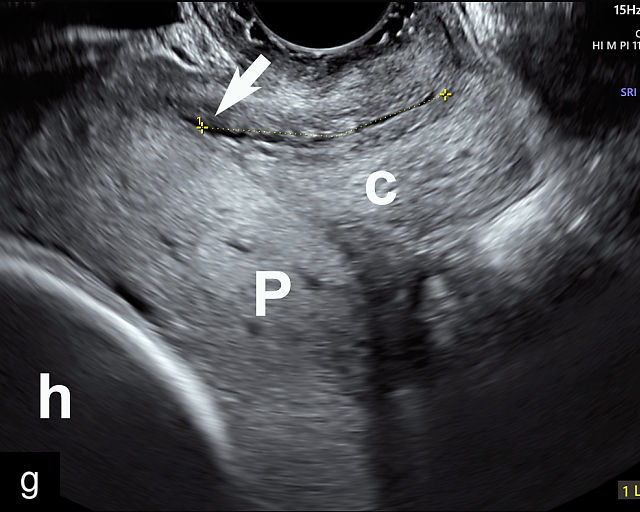

5

Placenta previa and low-lying placenta. (a) Transabdominal grayscale ultrasound image suspicious for placenta previa. The placenta (PL) appears to overlie the internal cervical os (CX). Note the time stamp: 2:19:37. (b) Transvaginal ultrasound of the same patient taken approximately 50 minutes later. Note the time stamp: 3:10:25. The internal os and the lower placental edge are both clearly seen, and the placenta does not overlie the internal os. Because the lower placental edge is 1.93 cm from the internal os, it will likely resolve by the third trimester. (c) Transabdominal grayscale ultrasound of placenta previa. The placenta (p) covers the cervix, but the cervix, especially the internal os, cannot be visualized due to shadowing. (d) Transabdominal grayscale ultrasound of placenta previa. The placenta (p) covers the cervix (c) but shadowing obscures adequate visualization. The internal os is indicated by the arrow. (e) False-positive image of placenta previa on transabdominal grayscale ultrasound. The bladder (b) is full, pushing the anterior and posterior walls of the lower uterine segment (ls) together making it appear that the placenta (p) overlies the internal os of the cervix. In reality, the line depicted by the arrowheads is where the anterior and posterior walls of the lower segment are in proximity to each other. The cervix is much lower and is obscured by shadowing (c). (f) Transabdominal grayscale ultrasound image of placenta previa. The placenta (p) covers the cervix (c), but the cervix, especially the internal os, cannot be visualized due to shadowing. b, bladder. (g) Transvaginal grayscale ultrasound image of placenta previa. The placenta (p) completely covers the internal os (arrow) of the cervix (c). The internal os can be seen clearly. h, fetal head. (h) Transvaginal grayscale ultrasound image of posterior low-lying placenta (p). The lower placental edge is clearly seen and is 1.56 cm from the internal os (arrow) of the cervix (c). The placental edge and the internal os are clearly seen. h, fetal head. (i) Transvaginal grayscale ultrasound image of a posterior placenta previa (p). The internal cervical os is clearly seen (arrow). c, cervix. (j) Transvaginal grayscale ultrasound image of an anterior placenta previa (p). The internal cervical os is clearly seen (arrow). c, cervix; h, fetal head. (k) Transvaginal grayscale ultrasound image of a posterior placenta that was thought to be low-lying on transabdominal sonography but could not be adequately assessed. This examination clearly shows the lower edge of the placenta (p) to be 2.18 cm from the internal os (arrow) of the cervix, firmly establishing that the placenta is not low-lying and allowing the patient to undergo labor safely and deliver vaginally. c, cervix. (l) Transvaginal grayscale ultrasound image of placenta previa. The placenta (p) completely covers the internal os (arrow) of the cervix (c). The internal os can be seen clearly.